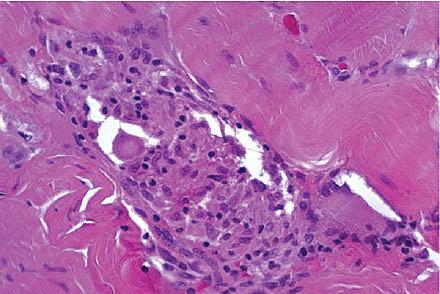

Sarkoidose er en almindelig systemisk inflammatorisk sygdom, som er karakteriseret ved dannelse af epiteloidcellegranulomer uden central nekrose. Sygdommen debuterer akut, typisk med feber, træthed, artralgi og hoste, eller subakut, hvor symptomerne kommer snigende og evt. manifesterer sig kronisk med permanent organskade. Incidensen af sarkoidose blandt skandinaviske kaukasider er 7,2/100.000 [1], hvoraf 80% har pulmonal sarkoidose. Ekstrapulmonale manifestationer forekommer (Tabel 1) og ses med øget hyppighed hos personer med anden etnicitet end kaukasid [2]. Hyperkalcæmi (HC) forekommer hos mindre end 5% af patienterne med pulmonal sarkoidose, mens solitær hyperkalcæmi som debutsymptom er sjældnere. Hyperkalcæmi afspejler ekstrapulmonal aktivering af T-celler i granulomer i hud, lever, terminale ileum og nyrer, hvilket fører til overproduktion af 1,25(OH)2D [2].

område med øget opladning bilateralt i m. biceps femoris. Der blev foretaget knoglescintigrafi og knoglemarvsbiopsi, og de var begge uden tegn til malignitet. Patienten blev udskrevet med uforklaret HC og blev fulgt ambulant. Tre måneder senere blev han genindlagt og overflyttet til et regionshospital med stigende S-Ca2+-niveau (til 1,84 mmol/l), men ellers var de biokemiske resultater uændret. Ekg viste sinusbradykardi og nyopstået højresidigt grenblok. S-ACE fandtes igen nedsat. ACE-hæmmerbehandlingen seponeredes, og S-ACE steg til værdier over referenceintervallet. En transtorakal ekkokardiografi viste asymmetrisk hypertrofi af septum med spættet udseende, hvilket gav mistanke om aflejringssygdom. En MR-skanning af cerebrum var uden tegn på cerebral sarkoidose. En biopsi af m. biceps femoris viste nonnekrotiserende granulomer, hvilket var foreneligt med sarkoidose. Der blev udført gastroskopi og analyse for parathyroidearelateret peptid, men der fandtes ikke holdepunkt for PET-CT-negativ malign sygdom. Der blev påbegyndt prednisolonbehandling, hvilket medførte et fald i S-Ca2+-niveauet samt et fald S-ACE-koncentrationen og aftagende symptomer. Patienten blev henvist til et sygehus med højtspecialiseret funktion til MR-skanning af cor, og kardiel sarkoidose blev udelukket.